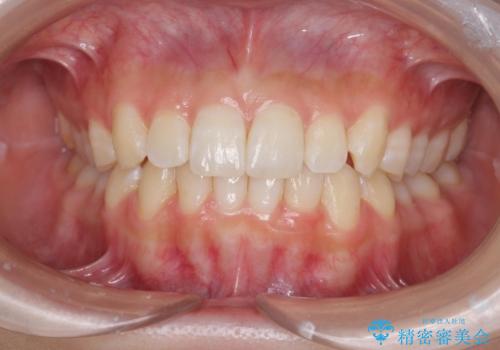

[マウスピース矯正] 海外留学中でも可能な矯正治療

担当医 大元洋佑